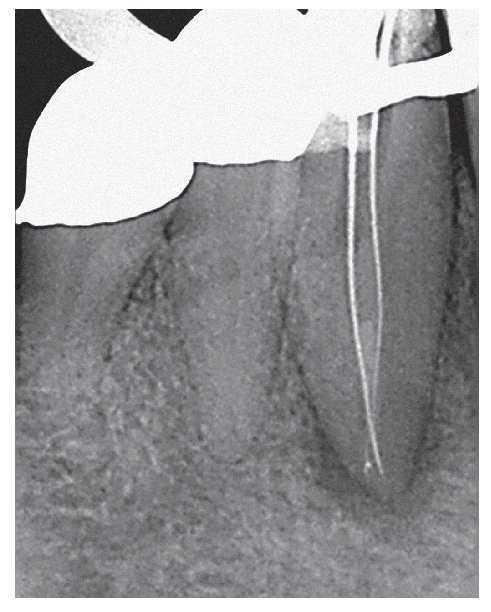

Figura 1a. Radiografía diagnóstica ortorradial del diente 43: una imagen radioopaca «interrumpe» el conducto radicular en el tercio medio de la raíz, fuerte curvatura apical del conducto radicular hacia mesial.

Figura 1b. En el segmento coronal de la raíz se observan dos conductos radiculares orientados en sentido vestibulolingual que están unidos por un istmo.

Figura 1c. En la proyección excéntrica de la conductometría se aprecia claramente la configuración tipo VI de Vertucci: los dos conductos radiculares están separados por un septo en el tercio medio y se unen nuevamente por debajo de éste mediante un istmo en el que se encuentran todavía restos de CaOH de la primera sesión. Los dos conductos muestran una trayectoria divergente en sentido apical para acabar en un foramen apical cada uno.